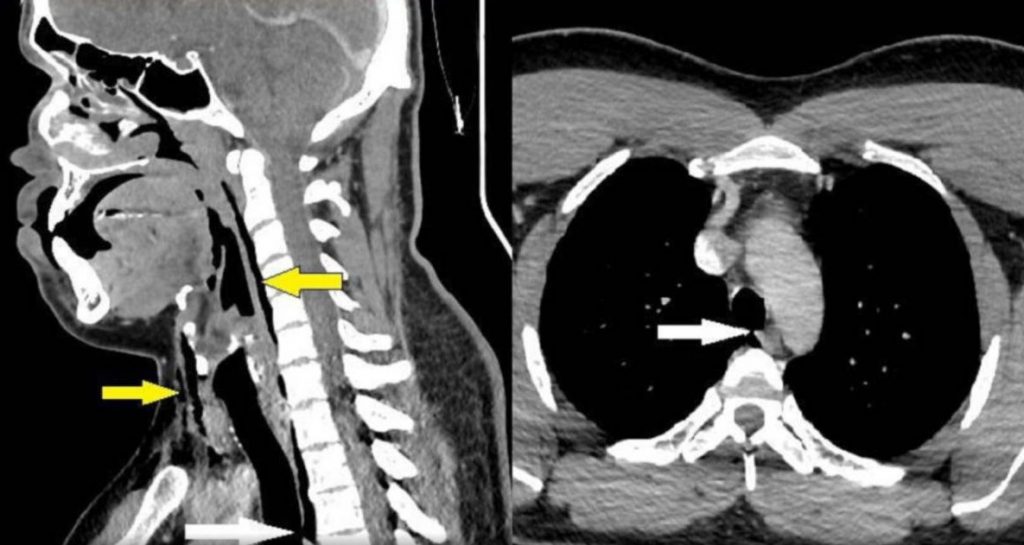

El paciente sufrió una perforación traqueal espontánea según el diagnóstico médico.

El paciente de 30 años sufrió una perforación traqueal espontánea por la fuerza del aire que expulsó su sistema respiratorio, según informó la publicación médica BJM Journals.

La herida en la tráquea del paciente tiene dimensiones de 2 milímetros x 2 mm x 5mm, y se encuentra entre la tercera y cuarta vértebra.